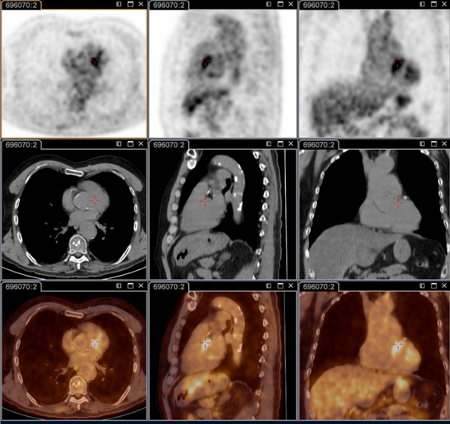

Q fever endocarditis diagnosed at PET scan: 18F-fluorodeoxyglucose PET/CT. In this asymptomatic patient with heart valve history with elevated serology, the PET scan diagnosed an aortic endocarditis on native valve with thoracic and lumbar aortic mycotic aneurysms

Institut Hospitalo-Universitaire Méditerranée Infection (patient consent obtained)